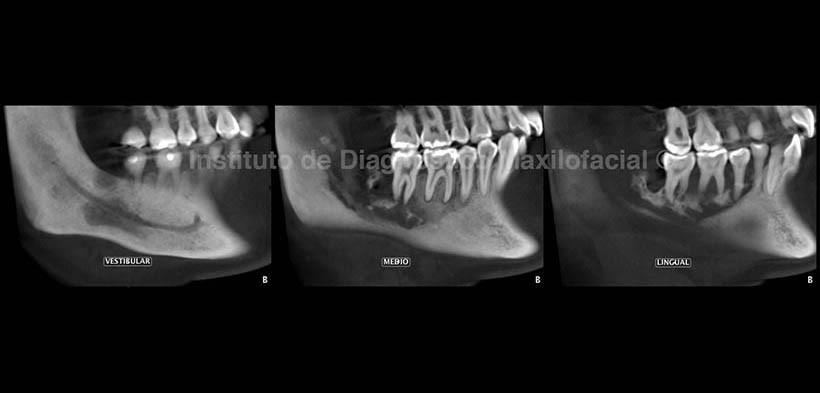

En la radiografía panorámica (Fig. 1) se observa una alteración del patrón trabecular en el lado derecho del maxilar inferior, caracterizado por áreas de rarefacción y de aumento de la densidad ósea a nivel de las piezas 4.5, 4.6 y 4.7; condicionando el ensanchamiento del espacio periodontal de éstas, y se extiende hacia el reborde alveolar de la pieza 4.8 compromete la zona antegonial, ángulo y rama ascendente.